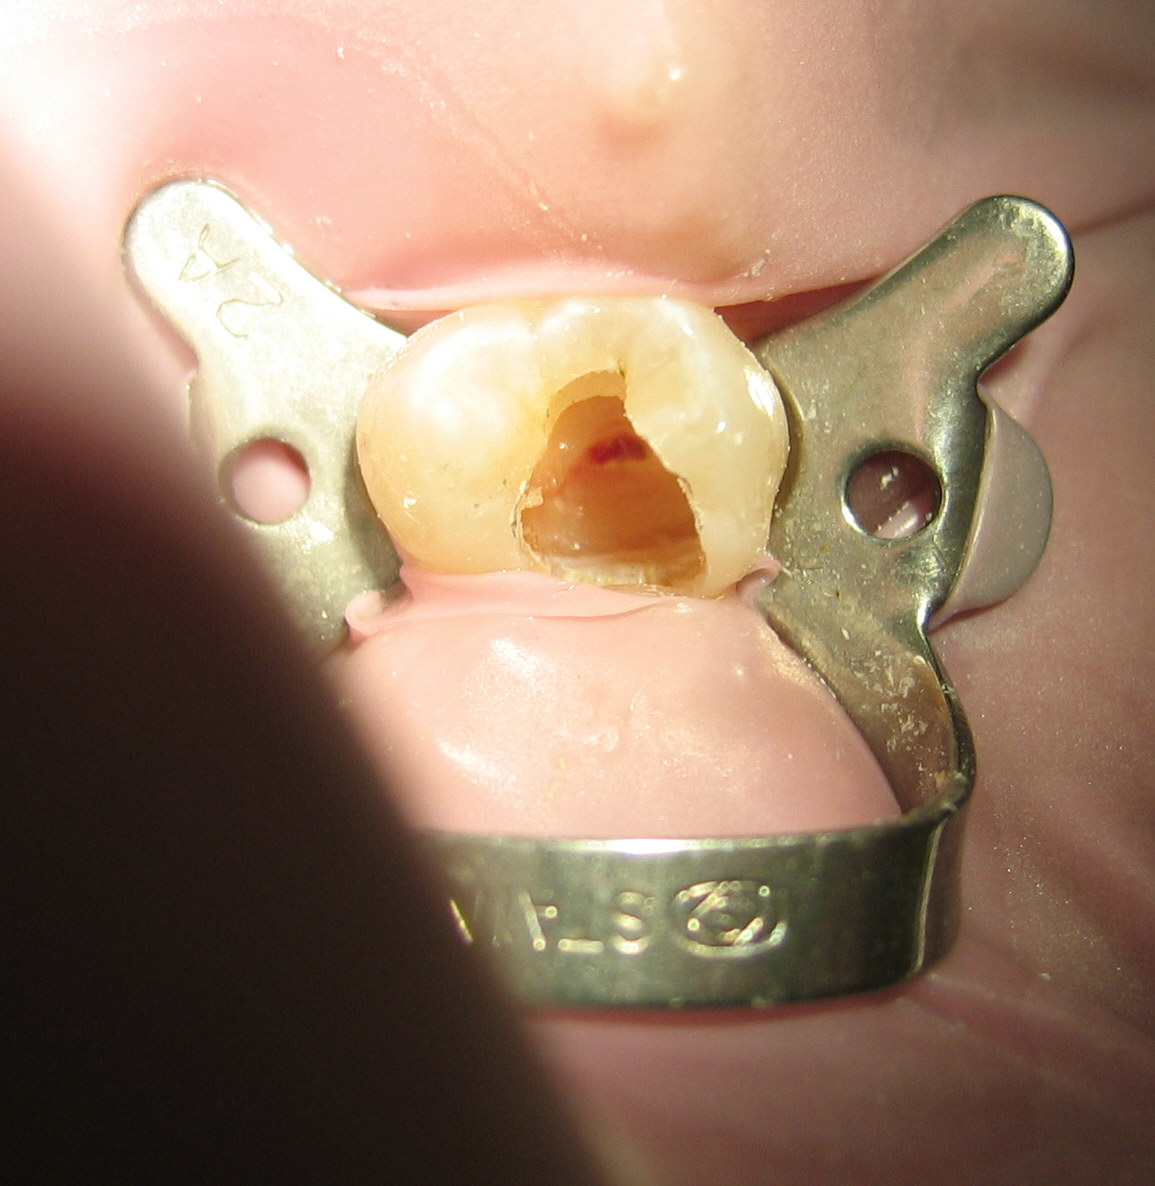

치수가 완전히 괴사한 경우에는 환자가 통증을 느끼지 못하므로 마취 과정을 생략할 수도 있다. 마취를 할 경우에는 공포심을 느끼는 환자를 위해 주사 전 마취 크림으로 표면 마취를 미리 해주는 것이 좋다. 또한 마취액을 주사할 때는 체온과 유사한 온도의 마취액을 가급적 천천히 일정한 속도로 주입하면 환자의 통증을 줄여줄 수 있다. 타액의 방습에는 솜말이(cotton roll)나 러버댐(Rubber dam)을 사용한다.

러버댐(rubber dam) 장착 가능 여부를 확인한다. 또한 교합면을 삭제해 근관 치료 과정 중 씹는 교합압 또는 저작압에 의해 발생할 수 있는 교합 외상을 피하고, 치아의 파절을 방지한다. 자연 치질의 벽이 부적절할 경우엔 인위적으로 벽을 형성해주고, 근관장 측정 시엔 일정한 기준점을 유지한다.

방사선 사진에서 치수강의 위치와 형태를 확인한 후 고속 핸드피스(high speed handpiece)에 라운드 버(round bur)나 #245, #330 버(bur) 등을 이용해 와동을 형성(cavity preparation)하고 치수강 내에 치수가 존재하는 경우 라운드 버(round bur)나 엔더단틱 스푼 엑스케베이터(endodontic spoon excavator)로 제거한다. 이때 치수실저(chamber floor)와 벽을 삭제하지 않도록 주의한다. 스무스 브로치(Smooth broach)나 근관 탐침을 이용해 근관의 입구를 찾고, 필요에 따라 추가적인 치과용 국소마취로 동통을 조절한다.

모든 치수(감염, 괴사되거나 건강한 치수)를 제거하는 것을 발수라고 한다.[132] 기구를 이용하여 치수강으로부터 치수를 완전히 제거하고, 근관이 넓고 치수가 생활력이 있으면 가시 브로치(barbed broach)를 사용하고 근관이 좁거나 치수가 괴사되어 있는 경우에는 파일(file)을 사용해 치수를 제거한다.